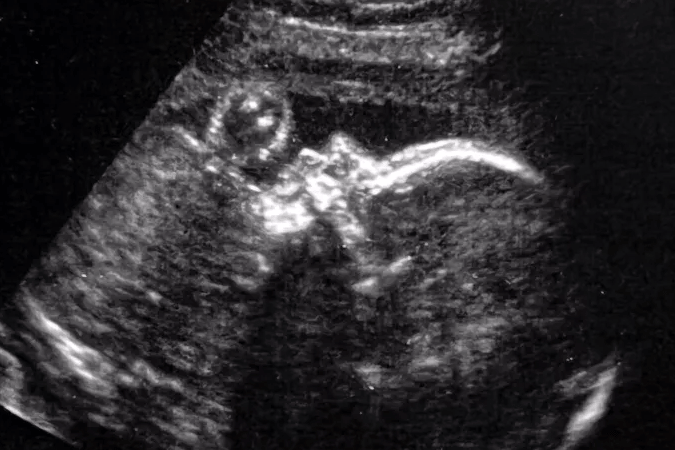

Η δυσπλασία συχνά αποκαλύπτεται κατά τη διάρκεια προγεννητικού υπερηχογραφήματος και διαγιγνώσκεται με μαγνητική τομογραφία κατά το τέλος του δεύτερου ή τρίτου τριμήνου της εγκυμοσύνης.